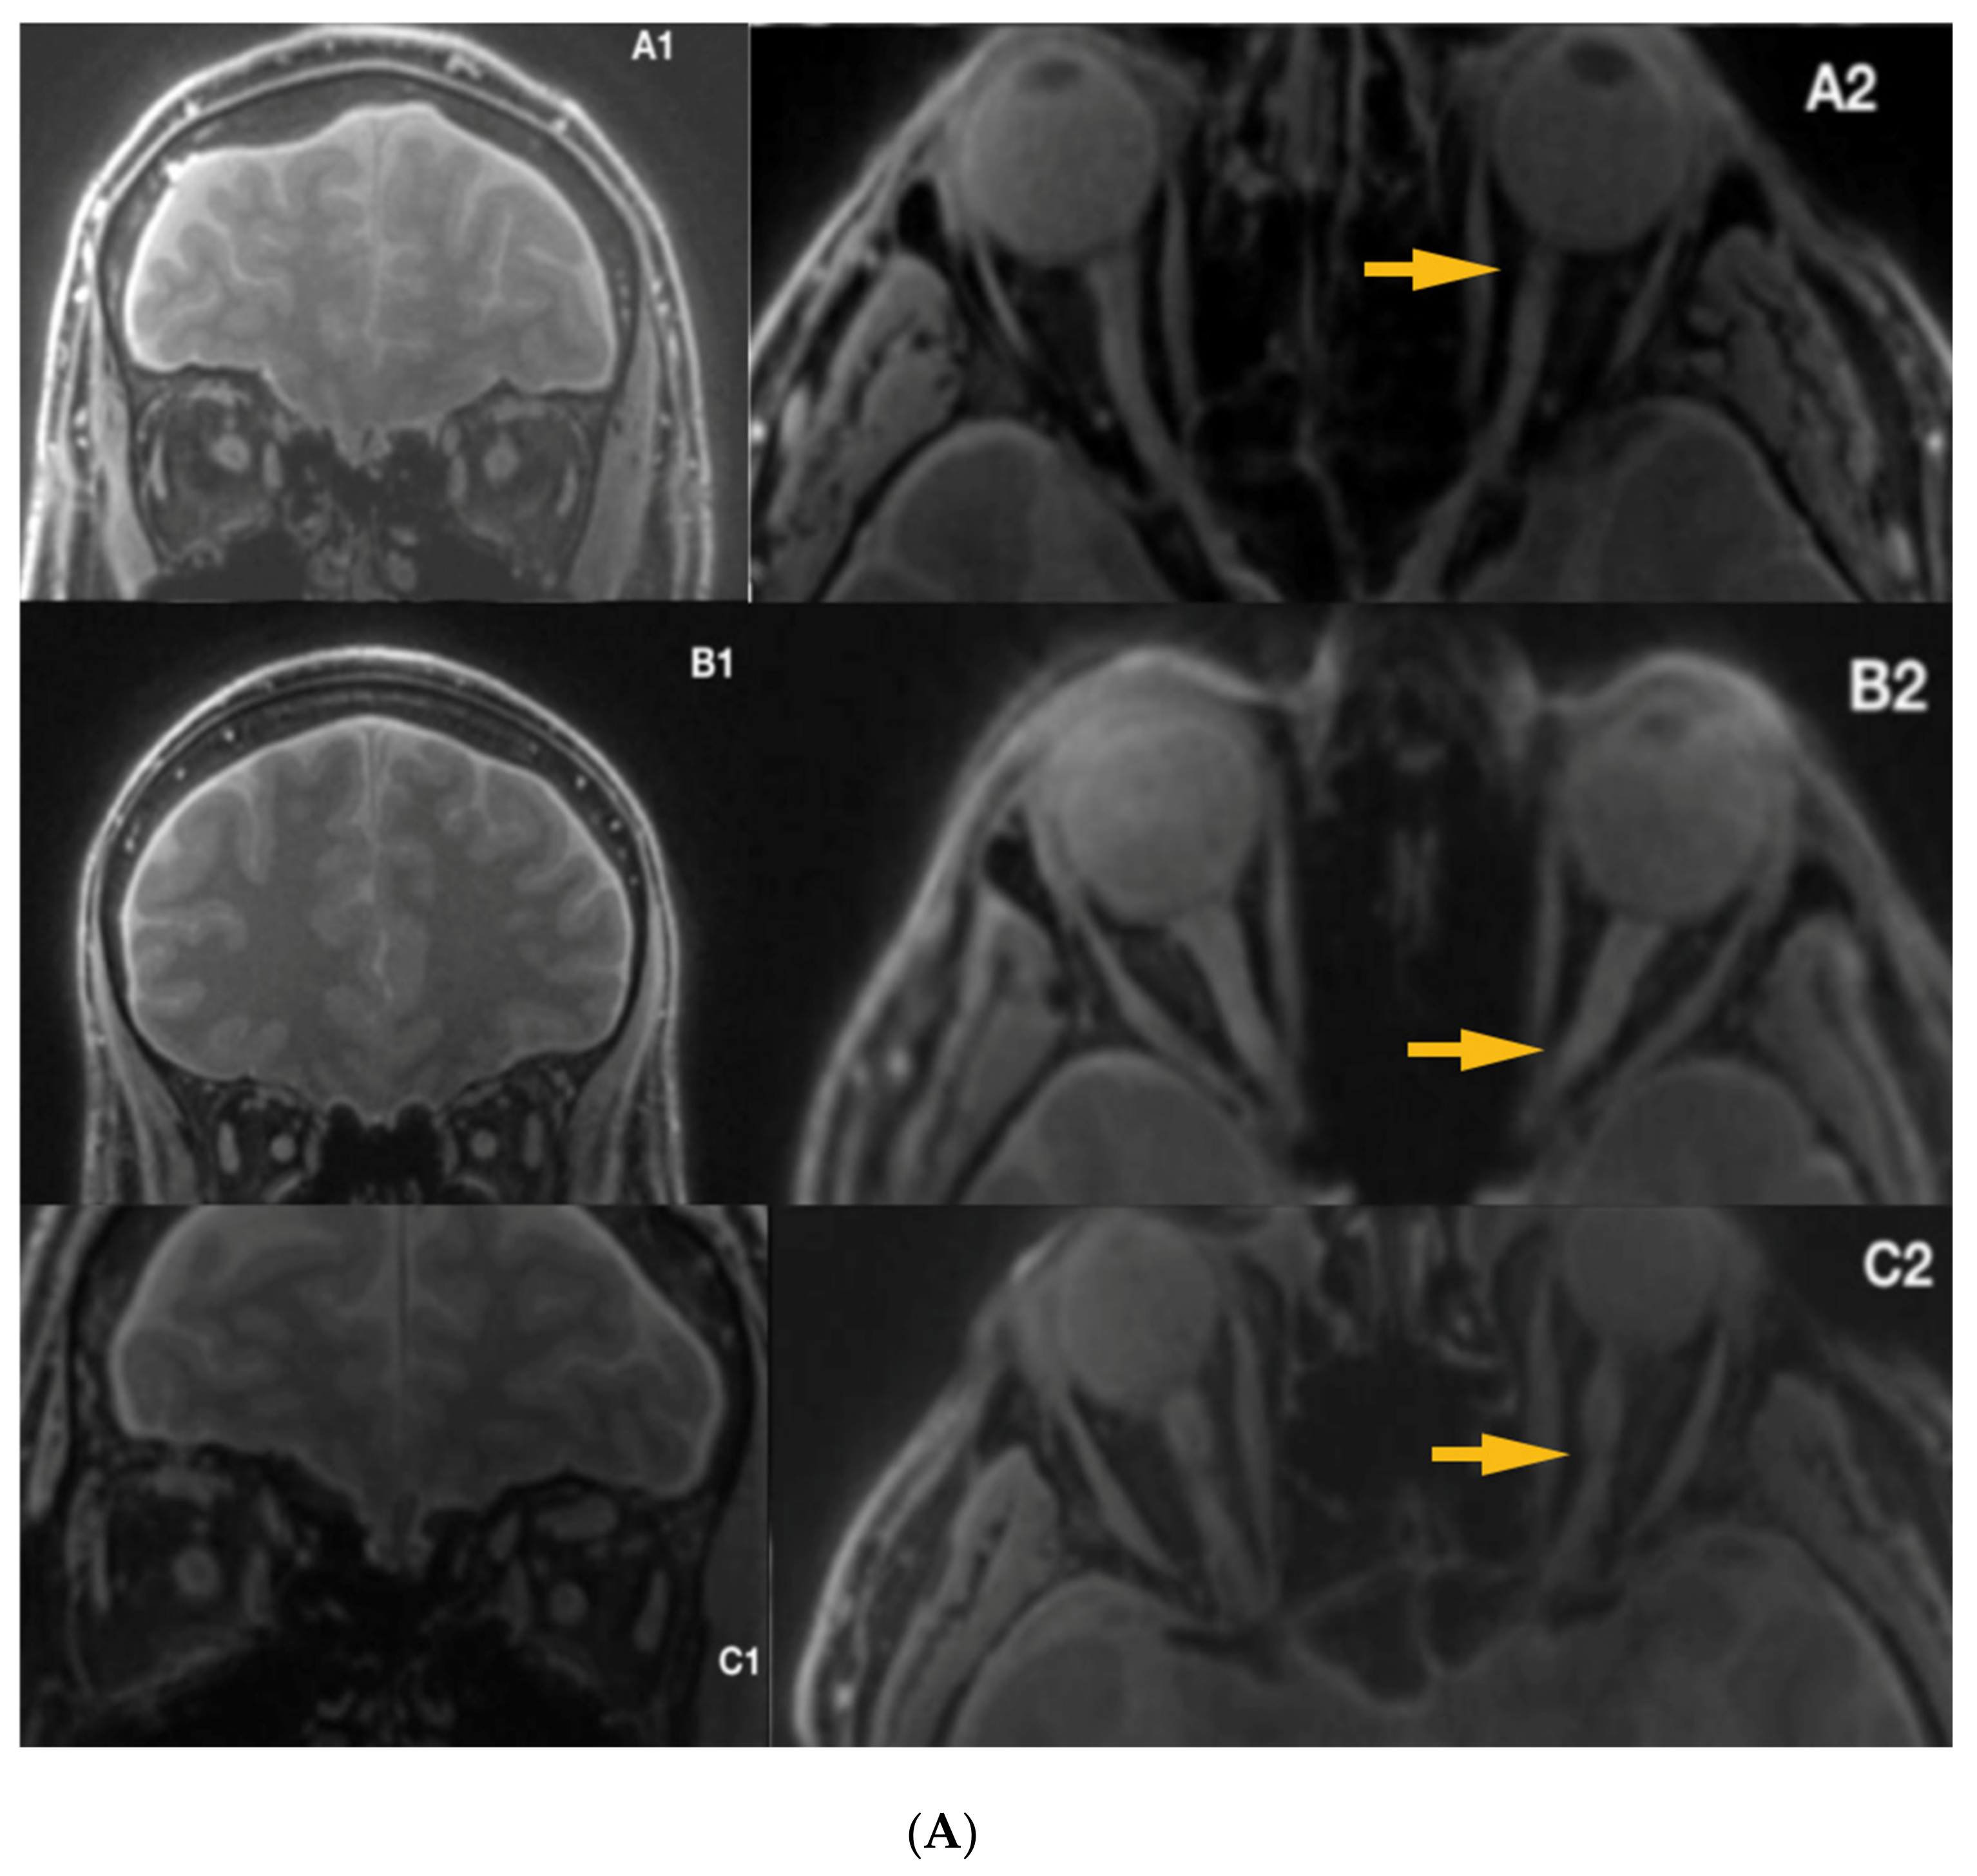

3.1. Radiological Inspection